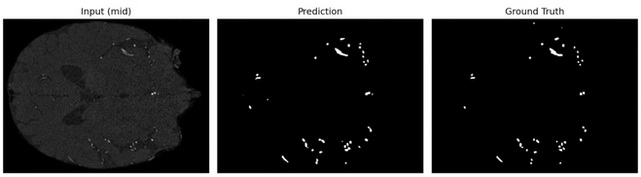

2D分割系統預測結果與 Ground Truth 高度接近,血管主幹與分支結構皆有良好還原,邊界清晰且雜訊較少,顯示模型已具備穩定的血管辨識能力。

(左)輸入的 MRA 影像

(中)對應的標註(Ground Truth)

(右)模型預測的分割結果(Prediction)

3D預測模型在 COSTA 資料集上,最終模型於61 筆測試影像達成 平均 Dice 0.8261 ± 0.0483,顯示分割穩定且具有泛化能力;從中片層對照可見主要動脈與多數分支均能被正確恢復,僅少數末端微細血管因訊號微弱或雜訊而出現斷裂。模型已具備穩定的血管辨識能力。

下面展示為測試集其中三組案例的中間切片預測結果:

(中)模型預測的分割結果(Prediction)

(右)對應的標註(Ground Truth)